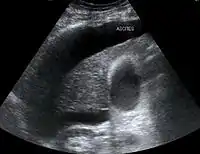

| Diagnóstico | Examen físico, ecografía, tomografía computarizada | |

Suele ser consecuencia de una enfermedad hepática, sobre todo la cirrosis hepática. El mecanismo de formación de ascitis más frecuente es la hipertensión portal consecuencia de cirrosis hepática alcohólica, cirrosis por hepatitis crónicas víricas de larga evolución como las causadas por el virus de la hepatitis B y por el virus de la hepatitis C o esquistosomiasis y se diagnostica clínicamente con el signo de la matidez desplazable, si bien la técnica más útil y reproducible es la ecografía abdominal.

- Ecografía